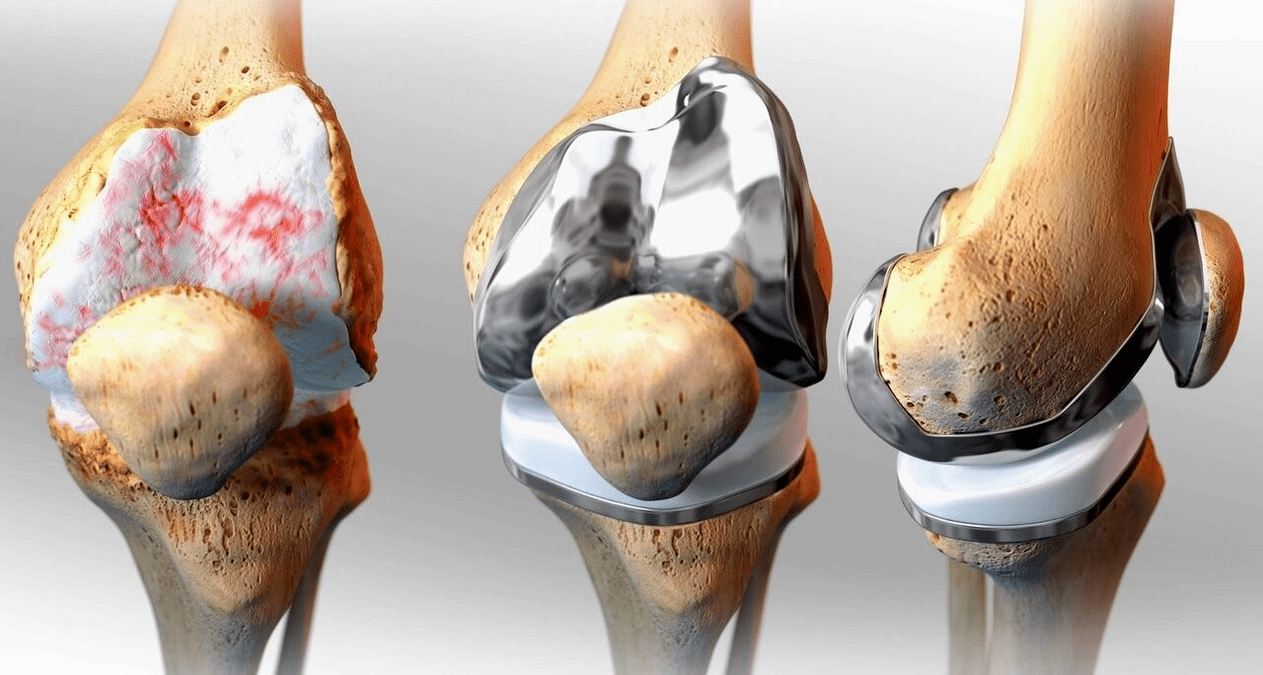

Surgical treatment and endoprosthetics

Endoprosthesis replacement is a common and effective surgical method for the treatment of severe gonarthrosis, which allows you to maintain limb mobility and the ability to lead a full life afterwards.This is a high-tech operation that takes about an hour and a half.In the postoperative period, long-term rehabilitation and development of the joint is necessary.After 25-30 years, when the artificial joint wears out, it needs to be replaced again.